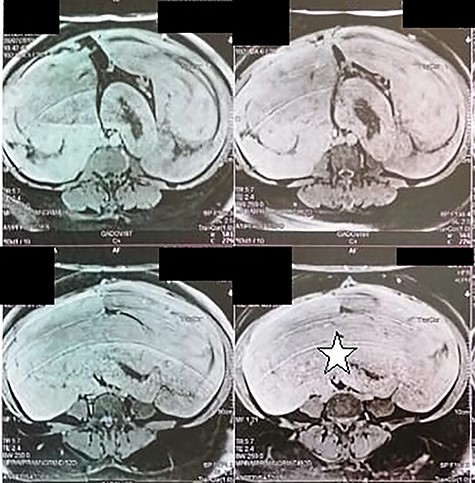

A 51-year-old woman presented to the department of surgery, with a 6 months history of an increasing pelvic heaviness and chronic constipation without urinary or gynecological disorders. Her medical history was positive for a total hysterectomy for multiple uterus fibroids, 8 years ago with no remarkable comorbidities. Upon physical examination, she had a palpable mass located in the left flank with a posterior and iliac extension. It was firm with regular borders. The patient’s blood cell counts, serum electrolyte levels, renal and liver functions, CA-125 and carcinoembryonic antigen were all within normal limits. Abdominal magnetic resonance image revealed a 32 × 29 × 12 cm retroperitoneal tissular mass with a signal that is isointense to that in muscle on T1-weighted images, and a homogeneous enhancement by contrast material (Fig. 1). The patient underwent surgical excision of the tumor. Careful exploration of the abdominal cavity revealed the retroperitoneal growth pattern of the mass extending from the pelvis to the flanks without adherences to adjacent structures. On gross, the specimen weighed 1660 g and measured 33 × 28.5 × 12 cm. It was well-circumscribed, firm, white-gray colored at sectioning. Hematoxylin–eosin-stained sections revealed mature smooth muscle cells with blunt-ended nuclei, and abundant eosinophilic cytoplasm arranging in intersected fascicles. The stroma contained vessels with mural hyalinization and myxoid changes (Fig. 2). Necrosis and nuclear atypia were absent. Mitotic count was 1/20HPF without atypical mitotic figures. On Immunohistochemistry, tumoral cells showed strong, diffuse positivity with smooth muscle actin (SMA) desmin, estrogen and progesterone receptors. They were negative for CD117, DOG1, PS100 and CD34 (Fig. 3). After surgery, the patient has had no recurrence (1 year).

Abdominal magnetic resonance showing a 32 × 29 × 12 cm retroperitoneal tissular mass with a signal that is isointense to that in muscle on T1-weighted images (white star).

Leiomyomas are smooth muscle benign tumors that rarely involve the retroperitoneum, and most of retroperitoneal tumors are believed to be malignant [5]. Billings et al. [6] have described two distinct subsets of deep soft tissue leiomyoma: (i) leiomyomas of somatic soft tissue which develop in extremities and (ii) retroperitoneal–abdominal leiomyomas. The latter occurs almost exclusively in women during the perimenopausal period [6] with (i) concurrent uterine leiomyoma or (ii) history of hysterectomy for uterine fibroids being, reported in up to 40% of the cases [7]. Clinically, presenting symptoms of retroperitoneal leiomyomas are often non-specific (including discomfort, fatigue, and back pain) or are related to compression of adjacent structures [1, 7]. as these tumors may extend to the upper retroperitoneum, being as high as the level of the renal hilum [7]. Pathogenesis of these lesions remains unclear. In fact, retroperitoneal leiomyomas might arise from the hormonally sensitive smooth muscle elements or the embryonal remnants of Müllerian and Wolffian duct might the cells of origin. They might also represent metastatic or synchronous primary lesions because only nine cases of this condition have been reported in men [1]. In our case, the patient had a history of hysterectomy for uterine fibroids; this supports the pathway of hormonally sensitive embryonal remnants or smooth muscle retroperitoneal elements. On imaging, magnetic resonance imaging (MRI) represents the most reliable technique for evaluating retroperitoneal masses. Classic leiomyomas are isointense to muscle on T1-weighted images and are hypointense to muscle on T2-weighted images, with homogenous enhancement. Although MRI is the most useful imaging modality for these tumors, histopathologic study is required to confirm the diagnosis, as in our case, where the anatomic origin of the mass could not be identified by MRI [7]. On gross, they range in size from 3.2 cm to 37 cm, and present as oval to spherical, well-circumscribed, lobulated, solid masses with a white to gray cut surface. Cystic degenerative and myxoid changes have been described in some cases [6]. Histologically, they share almost the same features with their uterine counterparts. The tumor consists of intersecting fascicles of spindled mature smooth muscle cells, with blunt-ended, or slightly tapered nuclei. The stroma contains numerous vessels with thick wall and mural hyalinization [4, 6]. Varying degrees of hydropic changes like those seen in uterine leiomyoma are present in the majority of tumors. Fatty changes, hyaline necrosis, myxoid changes, epitheliod or cord-like arrangement are commonly seen in retroperitoneal leiomyomas [4]. By definition, classic retroperitoneal leiomyoma lack of atypia, necrosis and significant mitotic activity (no >3 mitoses per 50 HPF) [5]. If mitotic activity is 5/10 HPF or more, these lesions are best referred to as ‘leiomyoma of uncertain malignant potential’; although high mitotic rates might still be compatible with benign condition. Definitive diagnosis requires immunostaining. Neoplastic cells are positive for SMA desmin and caldesmon. Positivity for CD34 has been reported in some cases, whereas tumoral cells are negative for CD117, S-100 protein and HMB45 [2]. Estrogen and progesterone receptors are typically positive [5].